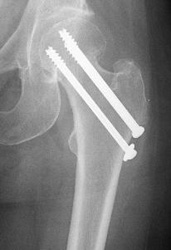

For true intracapsular hip fractures, the surgeon may decide either to fix the fracture with individual screws (percutaneous pinning) or a single larger screw that slides within the barrel of a plate. This compression hip screw will allow the fracture to become more stable by having the broken area impact on itself. Occasionally, a secondary screw may be added for stability.

If the intracapsular hip fracture is displaced in a younger patient, a surgical attempt will be made to reduce, or realign, the fracture through a larger incision. The fracture will be held together with either individual screws or with the larger compression hip screw.

Repair of an intracapsular fracture with individual screws.